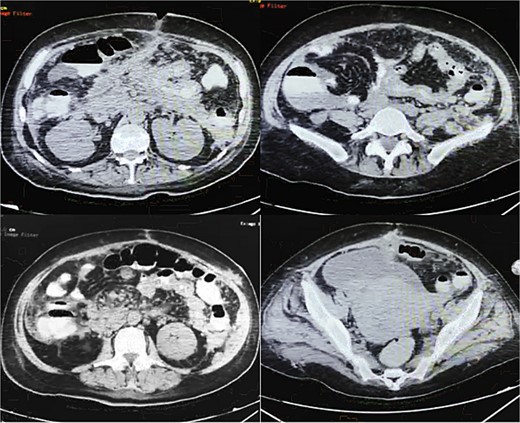

On POD 14, an oral contrasted abdominal CT scan was solicited; multiple pancreatic collections, the presence of a pseudocyst on the body of pancreas, an abscess on the tail of the pancreas, a fistulous tract from the pancreatic parenchyma directed to the surgical wound, and mesenteric vessels with counter clock-wise torsion below the transverse mesocolon (whirl sign) with small bowel loops near the ileocecal valve were observed (Fig. 3).

Oral contrasted abdominal CT with presence of abundant pancreatic collections on body and tail of pancreas with a volume of 132 ml, with evident fistulous tract from pancreatic parenchyma to abdominal fat and muscles near the surgical wound, torsion of mesenteric fat and vessels and terminal ileum loops in right abdominal space, free abdominal fluid on pelvic space.